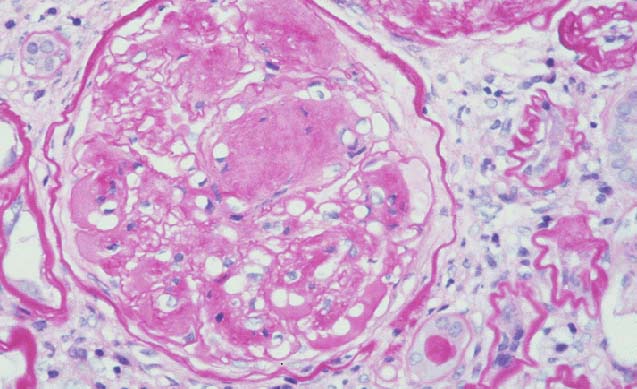

Overlap Fig A vs Fig B - Are these images from the same section? |

Fig A |

Fig B |